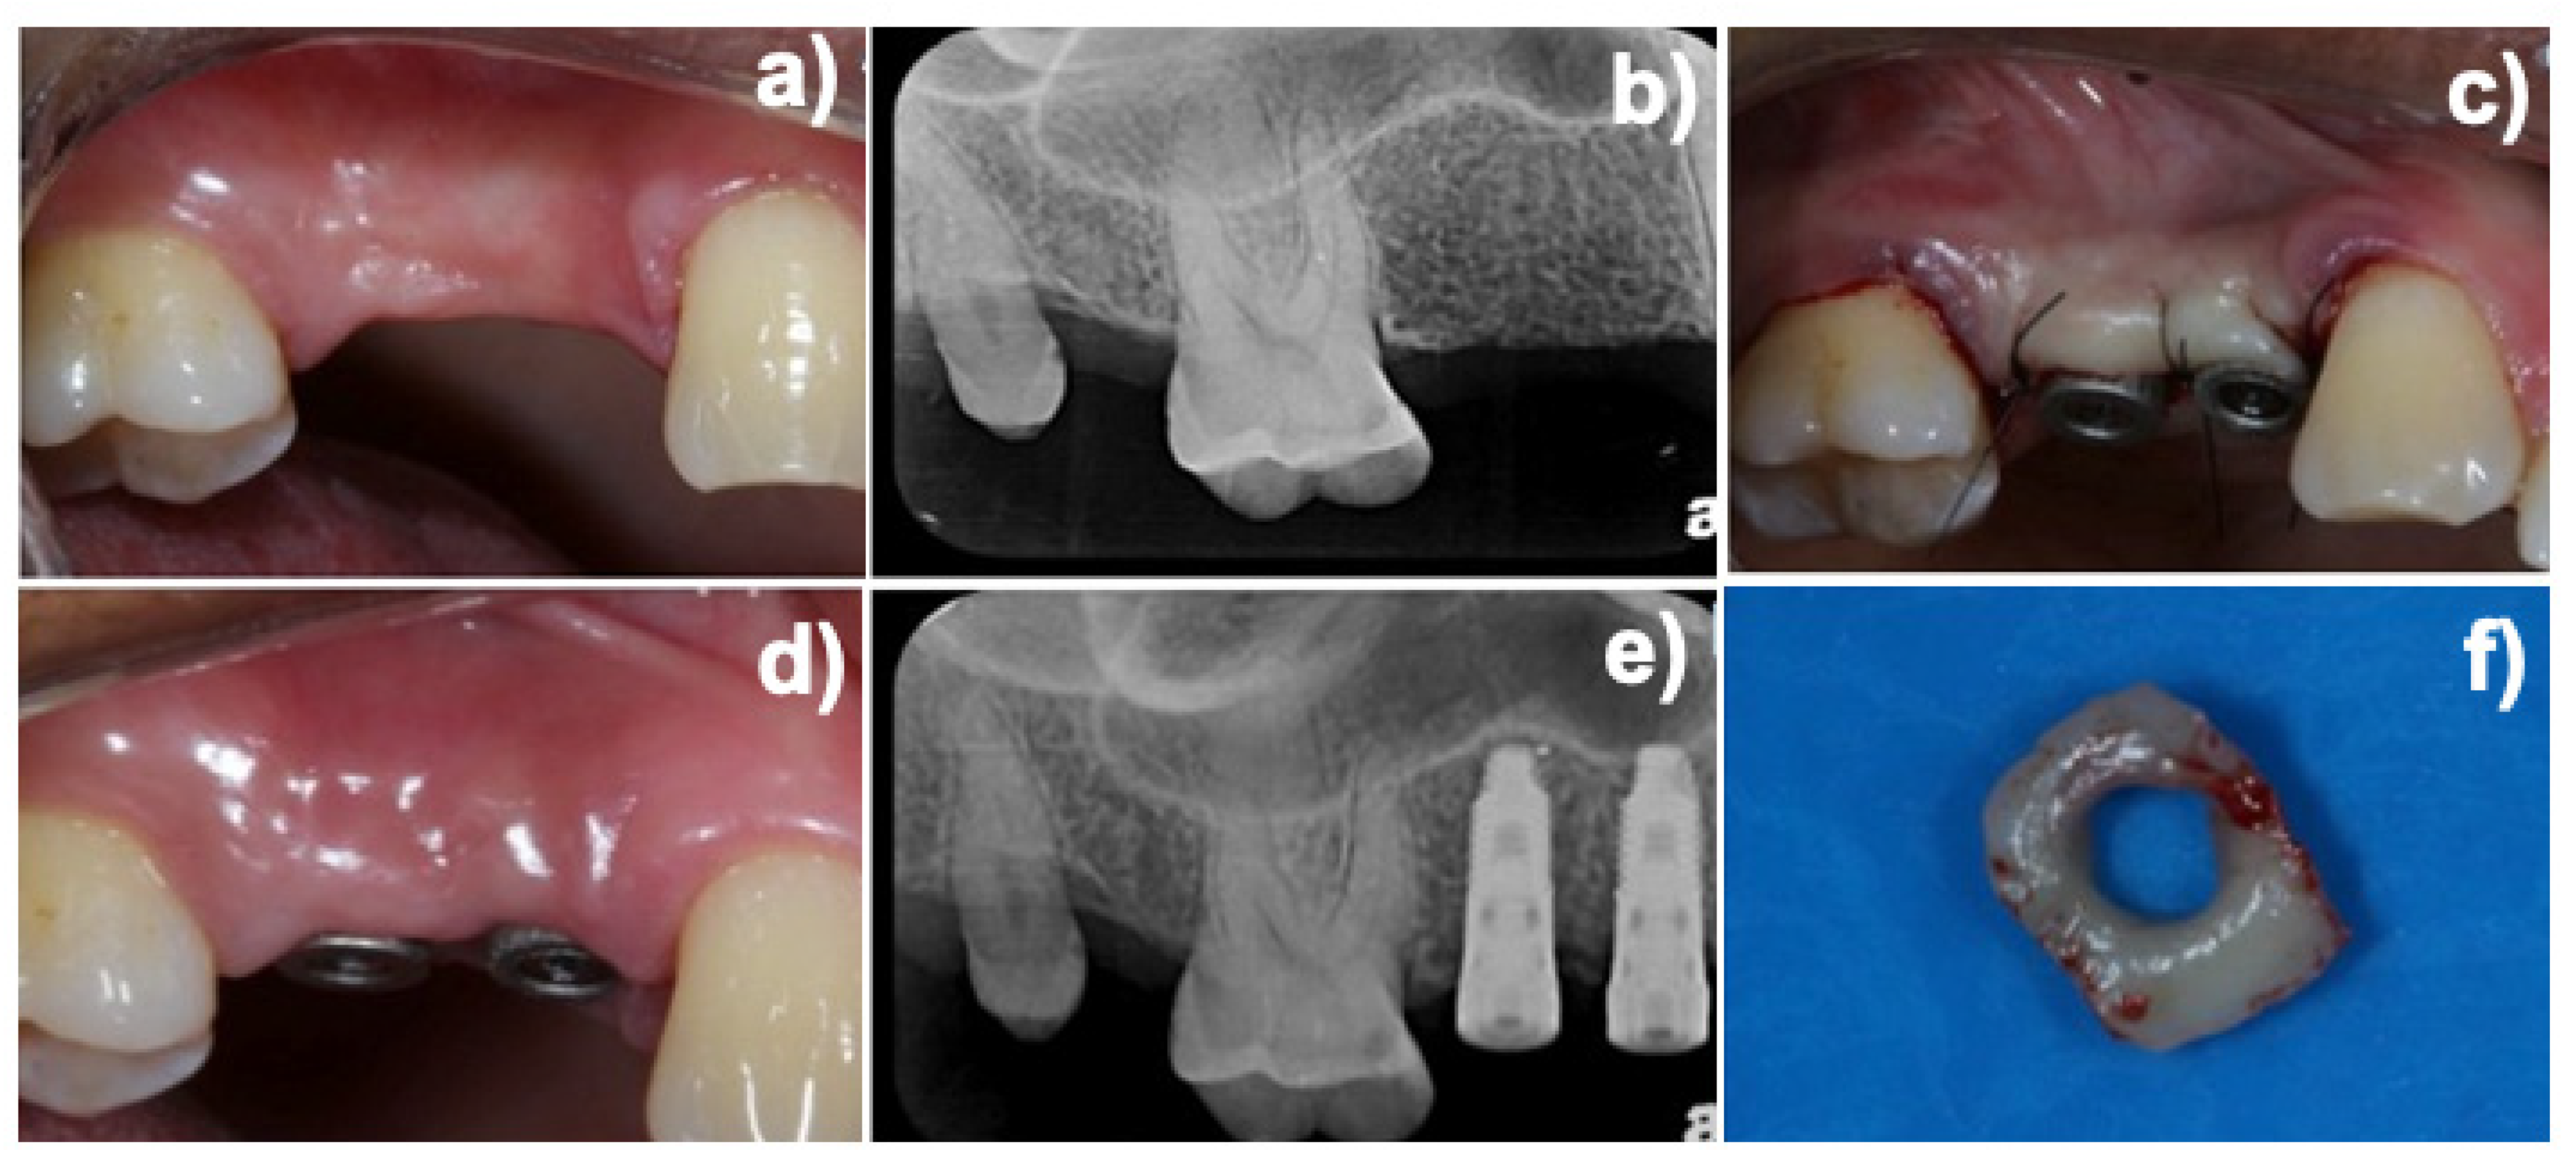

2. Materials and Methods

2.2. Experimental Design and Additive Manufactured (DMLS) Healing Abutment